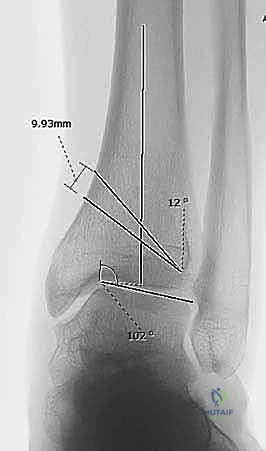

1. التخطيط الجراحي الدقيق (Pre-operative Planning)

يتم إجراء صور أشعة سينية خاصة (طويلة للساق بالكامل أثناء الوقوف) وأشعة مقطعية (CT Scan) ثلاثية الأبعاد. يقوم الدكتور محمد هطيف باستخدام برامج حاسوبية متقدمة لحساب الزاوية الدقيقة للتشوه، وتحديد حجم "الوتد العظمي" (Bone Wedge) الذي يجب إزالته أو إضافته لإصلاح المحور.